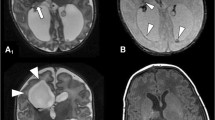

The suprathreshold stimulation intensity for MEPs was 500 V for TES and 30 mA for DCS. After establishing the baseline of c-MEPs preoperatively (left (Lt.) adductor pollicis brevis (APB): 36.7 µV, Lt. abductor hallucis longus (AH): 15.8 µV, right (Rt.) APB: 21 µV, Rt. AH: 15.7 µV), intraoperative MEP monitoring was initiated. Tibialis anterior and gastrocnemius were excluded from the study owing to the inability to obtain valid MEP waveforms. Detailed results are presented in Table 1. Post-hemispherotomy, MEPs could be measured from the left upper and lower extremities to the right cerebral hemisphere after TES. However, the MEP amplification effect of tetanic stimulation of the right median and tibial nerves was attenuated in both Lt. APB and Lt. AH, with MEPs reaching amplitudes similar to those observed at preoperative baseline (Fig. 2A, B). Both Lt. APB and Lt. AH also exhibited MEP amplification effects with pudendal nerve tetanic stimulation; however, the MEP amplification effect was significantly reduced post-hemispherotomy in Lt. AH (Fig. 2G, H). MEPs were not obtained during DCS to the right cerebral hemisphere, pre- or post-hemispherotomy, with or without tetanic stimulation.

Comparison of mean amplitudes between pre-hemispherotomy (pre-) and post-hemispherotomy (post) in each muscle and side of the tetanic stimulation group. The Mann–Whitney U test was employed for each comparison. A, B Transcranial electrical stimulation (TES) to the right cerebral hemisphere helped measure MEPs in both the left APB and AH, both pre and post. However, post-hemispherotomy, the MEP amplification effect of right peripheral nerve tetanic stimulation was attenuated in both the APB and AH. C, D TES to the left cerebral hemisphere enabled stable MEPs to be obtained throughout the surgery. E, F Notably, left tetanic stimulation resulted in significantly higher right AH and MEP in Post than that in Pre. G–J Overall, the MEP amplification effect was observed in the p-MEP group; however, in the right-side TES, the MEP amplification effect of AH was significantly attenuated in post. *p < 0.05, **p < 0.01. APB, adductor pollicis brevis muscle; AH, abductor hallucis longus muscle; mt, tetanic stimulation of the unilateral median and tibial nerves; MEP, motor-evoked potential; p, tetanic stimulation of the pudendal nerve; TES, transcranial electrical stimulation

TES to the left cerebral hemisphere enabled the acquisition of stable MEPs in the right upper and lower limbs throughout the surgery (Fig. 2C, D; I, J). mt-MEPs and p-MEPs demonstrated similar amplification effects compared with that of c-MEPs. Post-hemispherotomy, tetanic stimulation of the left median and tibial nerves exhibited an amplifying effect on right upper and lower limb MEPs during TES to the left cerebral hemisphere; Rt. AH exhibited significantly higher amplification than pre-hemispherotomy (Fig. 2E, F).